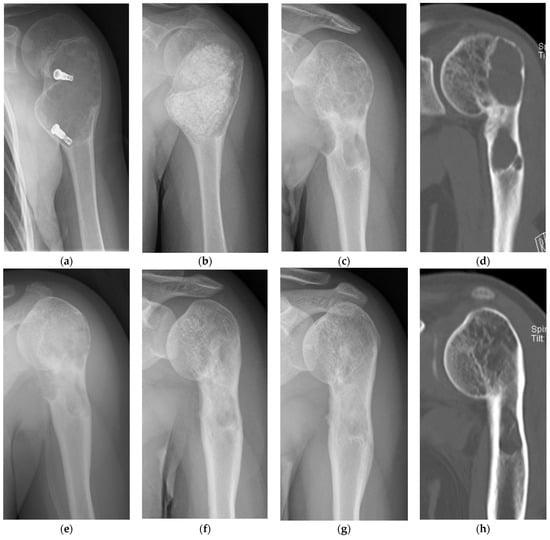

- Sotome, S.; Ae, K.; Okawa, A.; Ishizuki, M.; Morioka, H.; Matsumoto, S.; Nakamura, T.; Abe, S.; Beppu, Y.; Shinomiya, K. Efficacy and safety of porous hydroxyapatite/type 1 collagen composite implantation for bone regeneration: A randomized controlled study. J. Orthop. Sci. 2016, 21, 373–380. [Google Scholar] [CrossRef]